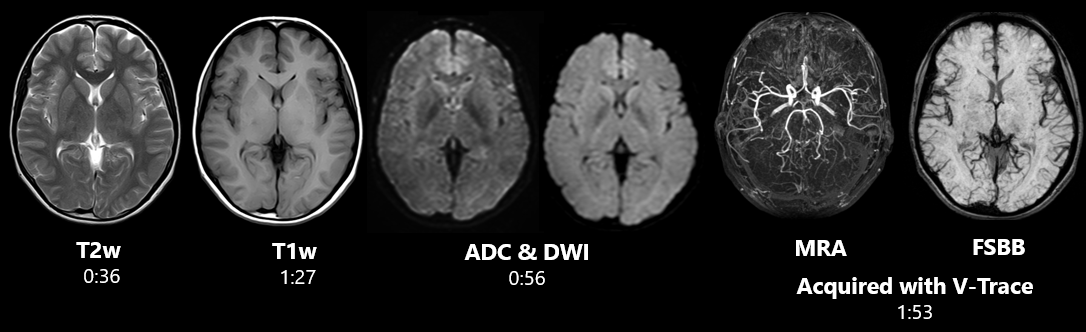

Загальна радіологія

Обстеження головного мозку за короткий час доступне з Vantage Elan 1.5T. Завдяки поєднанню базових технологій ATLAS, Pianissimo™, SPEEDER проведення досліджень займають мінімум часу та надають максимум комфорту для пацієнта. Завдяки поєднанню різних анатомічних котушок.

Безшовність отриманих зображень

Мінімальна кількість етапів для сканування всього пацієнта.

Результат – скорочення часу дослідження